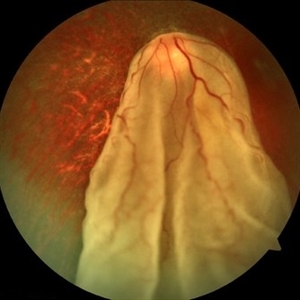

Total Rhegmatogenous Retinal Detachment With Severe PVR

May 27 2015 by Darin R. Goldman, MD

63-year-old pseudophakic male with hand motion vision in the left eye due to a total retinal detachment with severe proliferative vitreoretinopathy.

Condition/keywords: proliferative vitreoretinopathy (PVR), retinal tear